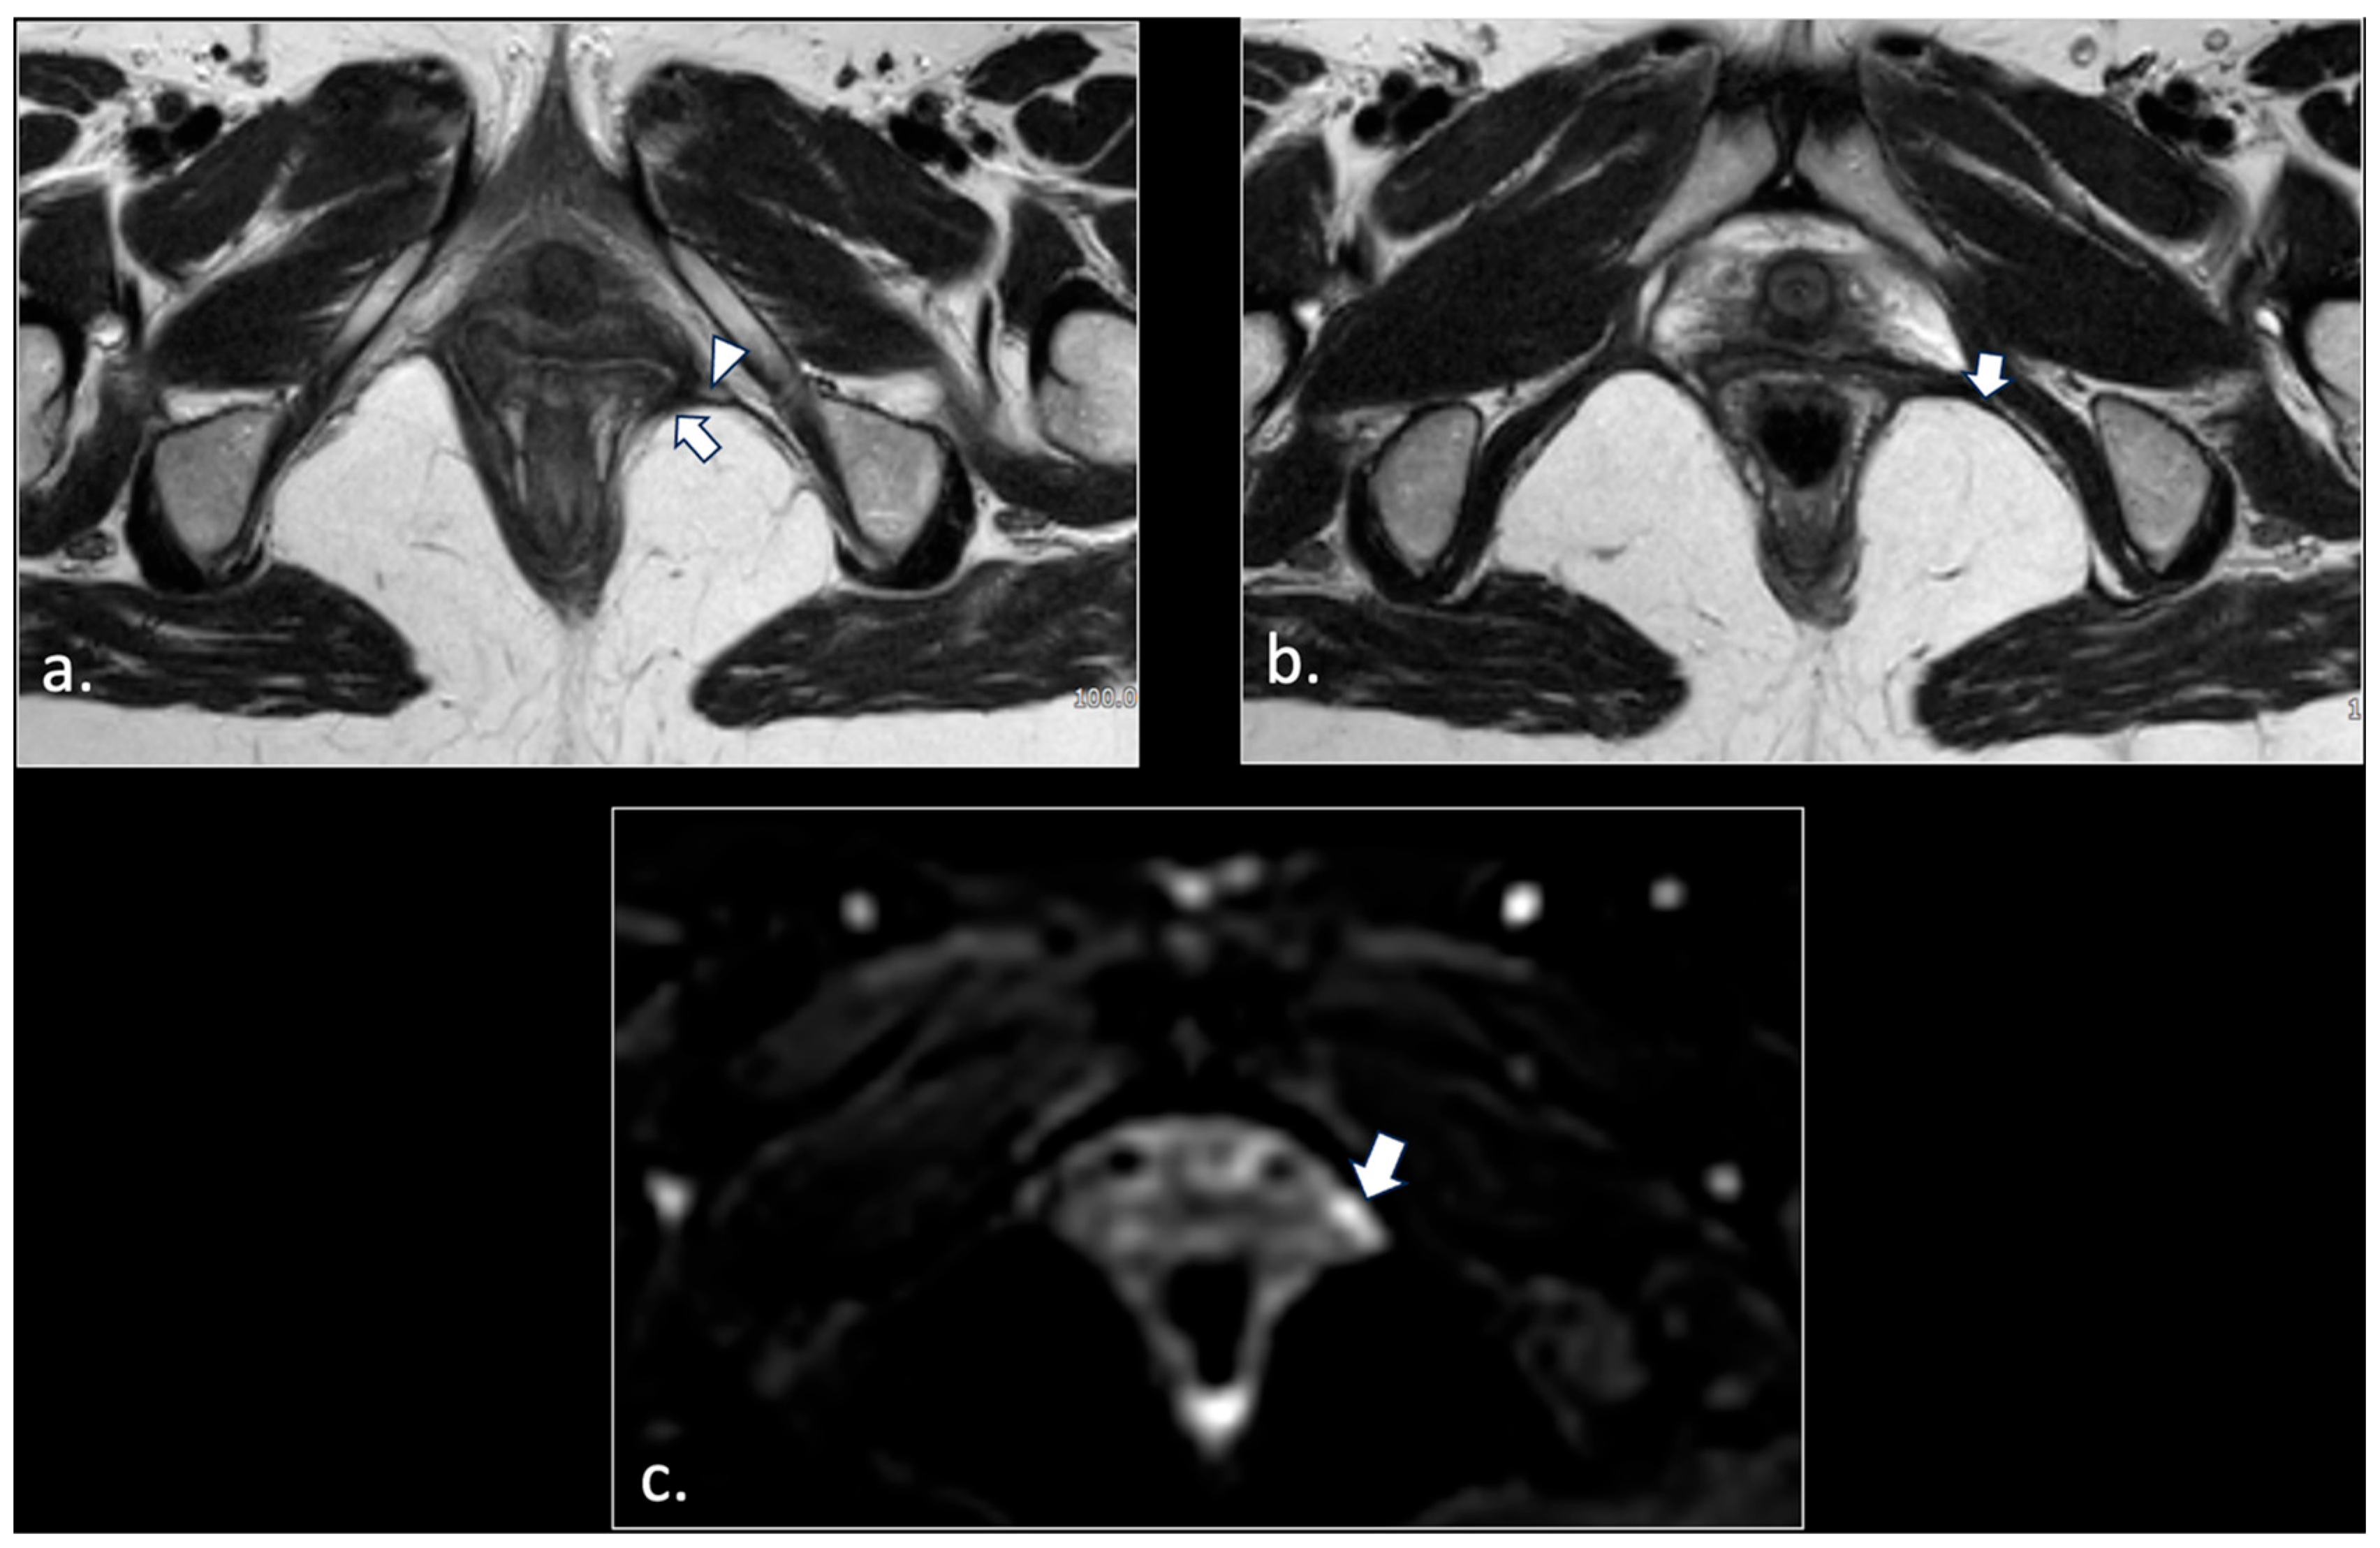

- Unilateral or bilateral lesions of the sacrotuberous and/or sacrospinous ligaments (interligamentous space) (5 patients);

- Perineal fibrosis involving Alcok’s canal (4 patients);